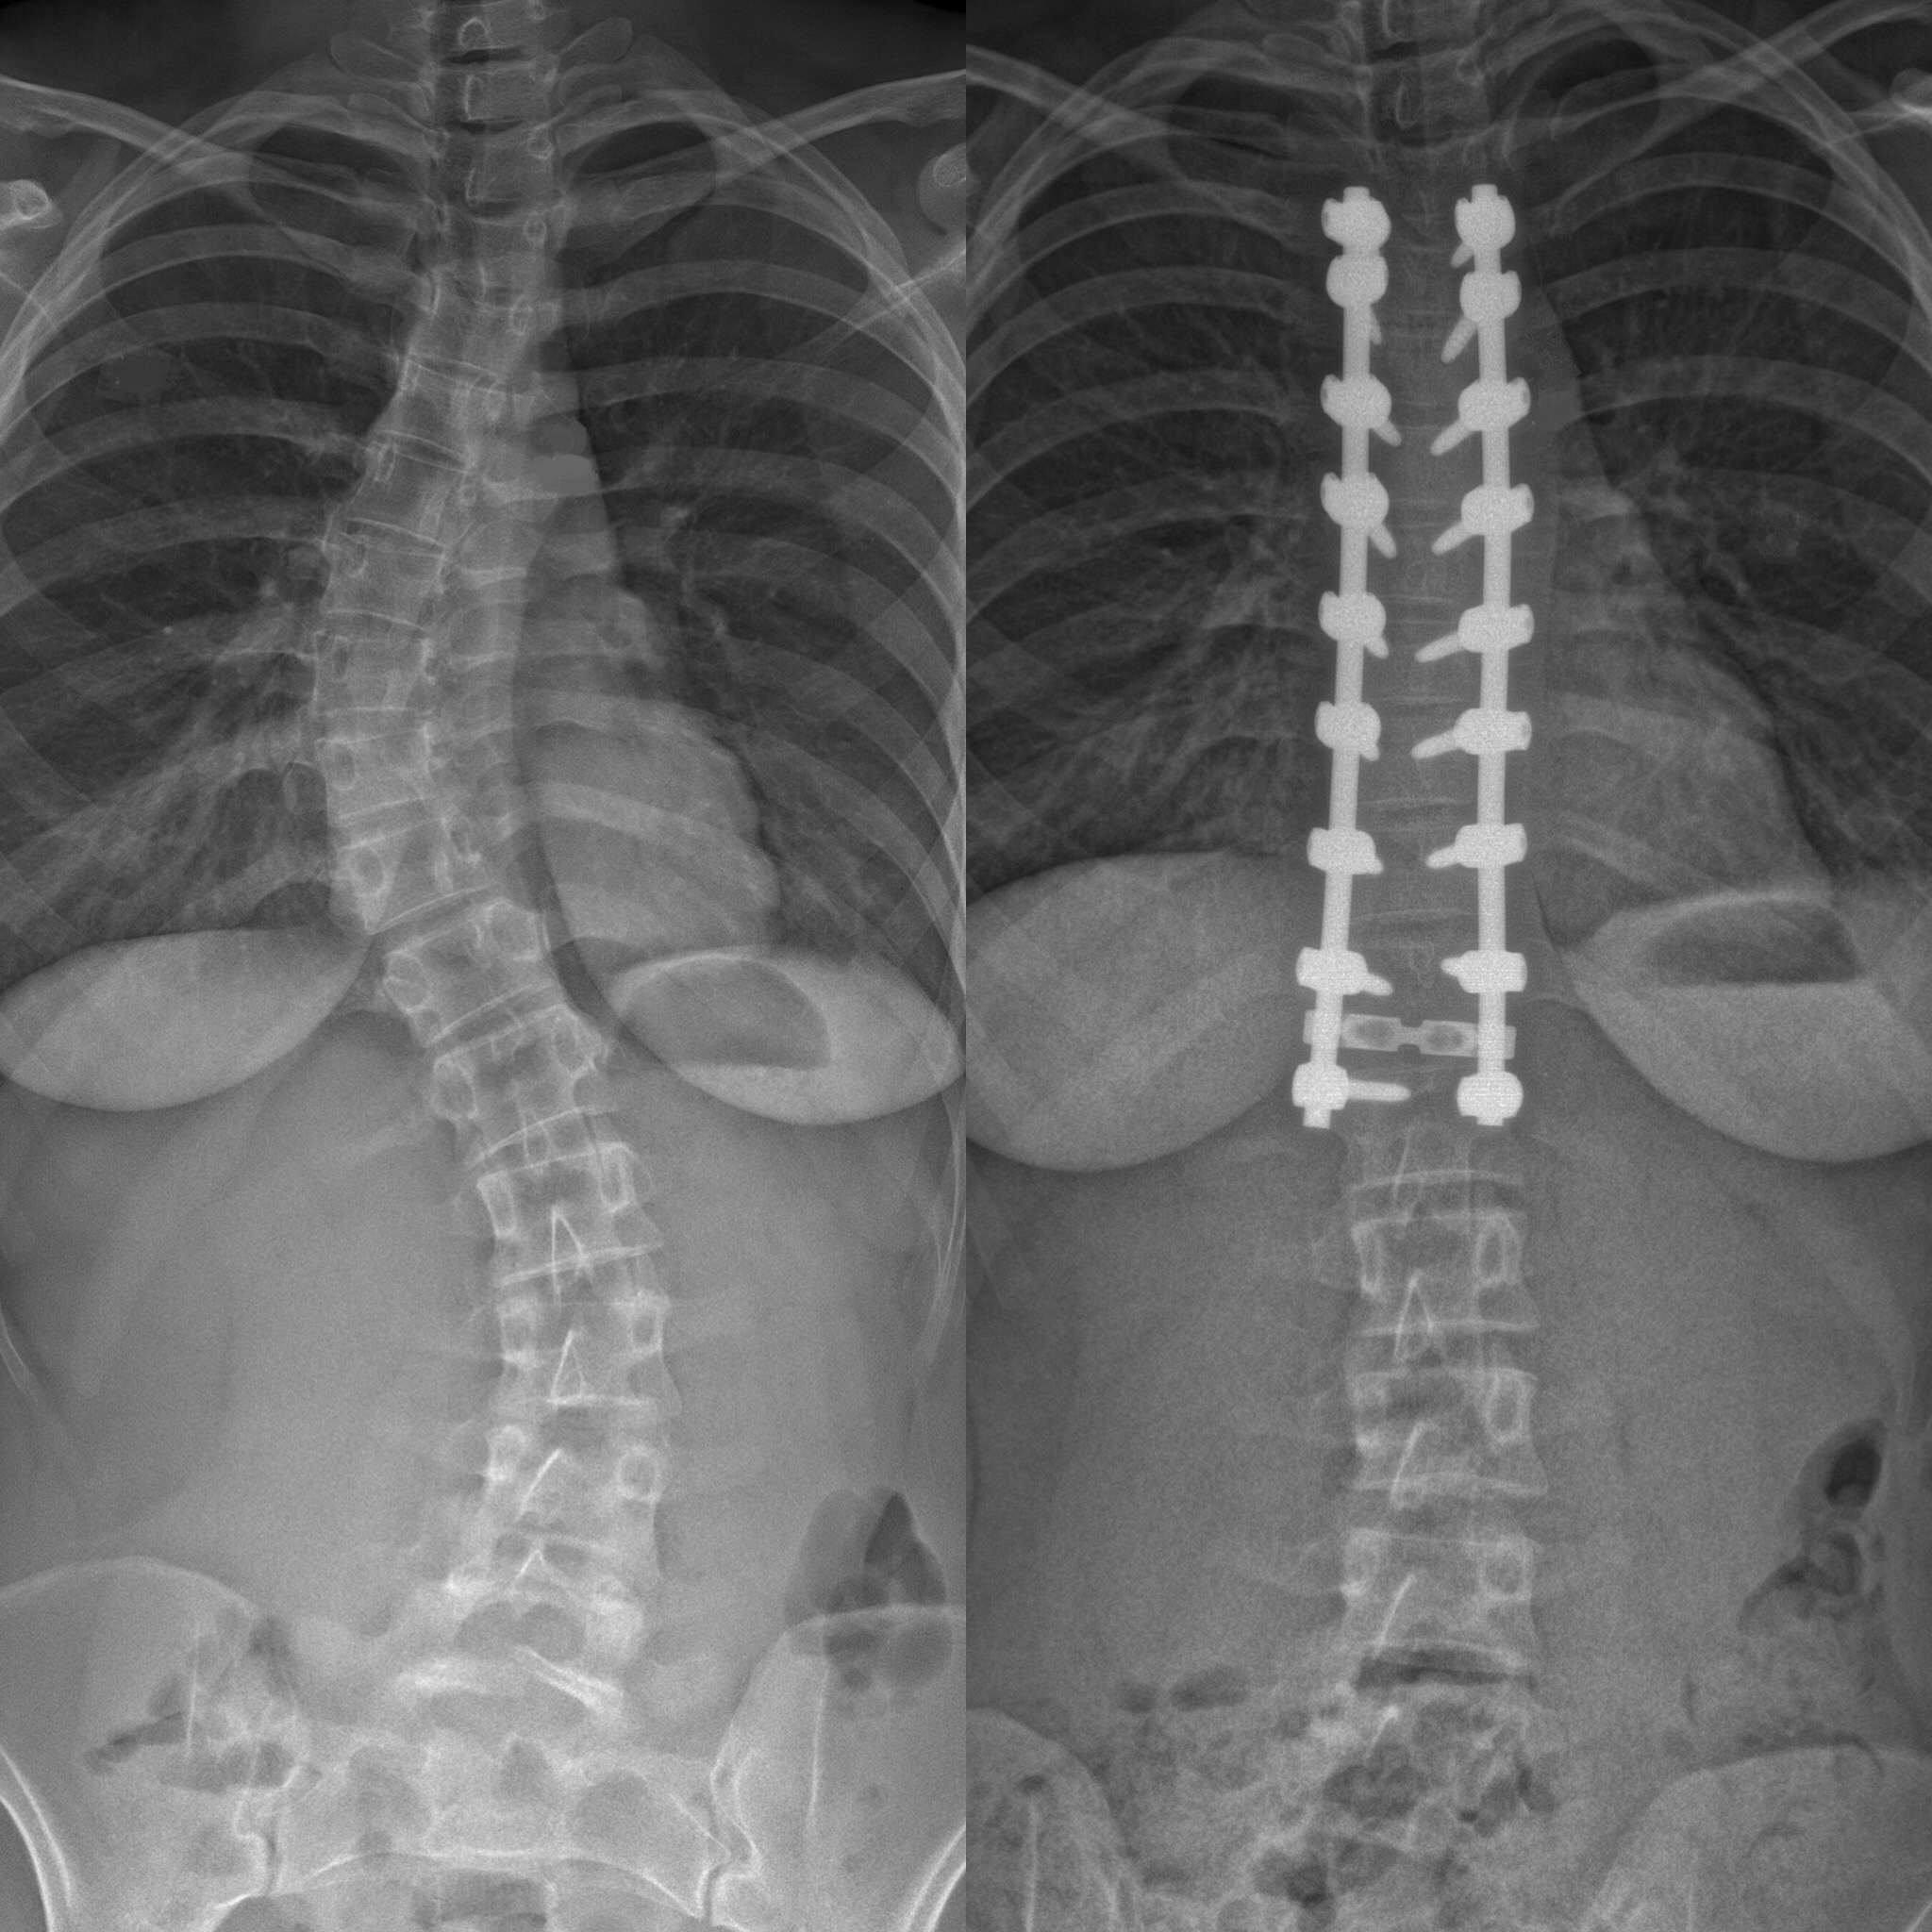

Skolios är en sidoförskjutning av ryggen på mer än 10 grader som mäts på en röntgenbild.